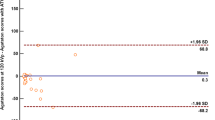

Overall, there was a very good correlation between scores calculated with 120 and 80 kVp tube voltage scans (R = 0.94, R2 = 0.88, P > .001). Bland–Altman limits of agreement of − 563.5 to 871.9 and a bias of − 154.2 (Figures 1, 2).

There was a difference between the proportion of patients assigned in the < 25% percentile class (P = .03) (25.0% in standard CT acquisition vs 39.1% in low-dose CT acquisition). Conversely, the proportion of patients assigned to the percentile classes other than < 25% did not differ between the two acquisition protocols. The results are summarized in Table 2 and in Figure 3.

Moreover, we found a significant difference in the proportion of patients with CACS = 0 between standard acquisition (n = 264, 17.5%) and low-dose scan (n = 437, 28.9%, P < .001). The 437 patients with CACS = 0 with the low-dose scan had CACS ranging between 0 and 372 (median 0, IQR 0 to 4). Among patients with CACS = 0 in the low-dose imaging, 173 had CACS > 0 on the standard acquisition. Of note, these 173 patients are mostly coming from the < 25% risk class as assessed with the standard protocol. In only 9/173 Patients (5%) the standard acquisition showed markedly higher values (i.e., from the 25% to 50% risk class, median 6, IQR 1 to 3).

In this regard, there is a discrepancy between the results of our study and those reported in the literature. In fact, we found a systematic underestimation of calculated CACS if 80 kVp tube voltage was used. As a consequence, the number of patients assigned to the low (< 25%) percentile class was different between the two protocols, being higher for low-dose acquisitions. Additionally, also the proportion of patients with CACS = 0 was different between the two acquisition protocols. The discrepancy may relate in a difference in the patient sample size, being ours larger by a factor of 10 compared with the previous reports. Another possible explanation is the impaired recognition of smaller calcifications with the low-dose protocol, possibly due to increased noise and consequent loss in spatial resolution. In a recent study, reducing the kVp tube voltage caused an increase in image noise by a factor 1.9 and 2.5 at 80 and 70 kVp, respectively.18 Due to image blurring and the concomitant impact of partial volume effect (PVE),19 it is conceivable that some tiny lesions are missed in low-dose protocols, and this becomes evident when larger patients’ samples are investigated.

In this regard, our results show that the greatest difference and spread in CACS between the two scores becomes more evident in the progressively higher scores and not in the very lowest percentile groups. This observation seems to rule out increased noise as major determinant of underestimated CACS, as the impact of noise should be more evident for small calcifications, as seen in lower CACS. However, as CACS equals the sum of scores of all calcifications, then higher CACS often results from multiple lesions. As a real calcification can be missed or underestimated if a blurred image causes a spread of its appearance, the same repeated error on multiple calcifications would amplify the bias in the calculation of global CACS with consequent underestimation, which intuitively becomes more evident if a large patient population is investigated.